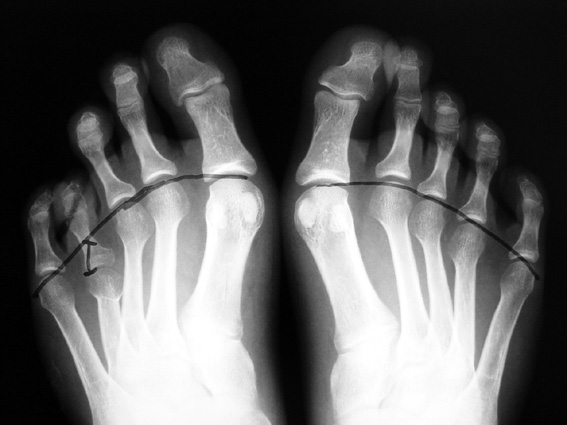

El parmağı (metakarp) ve ayak parmağı (metatars) kısalıkları doğuştan tek başına, geniş bir sendrom grubuyla birlikte, travma sonrası, Freiberg hastalığı (avasküler nekroz) sonrası görülebilir.

Doğuştan metakarp ve metatars kısalığının görülme sıklığı 1/1000’den azdır. Kadınlarda erkeklere göre 5 kat daha fazla görülür ve sıklıkla (%72) iki taraflıdır. En sık 4. parmak tutulur. Bu tür olgularda sorunun nedeni tam olarak bilinmemekle brlikte deformitenin genellikle epifiz plağının erken kapanmasından kaynaklandığı düşünülmektedir.

Doğuştan metakarp ve metatars kısalıklarının redavisi için pek çok teknik tanımlanmakla birlikte en çok akut uzatma sonrası kemik uçlarına greft konması ve distraksiyon osteogenezi (kallotasis) kullanılmaktadır. 1 cm.den daha fazla uzatma gereken olgularda kallotasis yöntemi önerilmektedir. Kliniğimizde de metatars ve metakarp uzatma için unilateral eksternal fiksatör ve sirküler eksternal fiksatör yardımıyla distraksiyon osteogenezi yöntemi tercih edilmektedir.